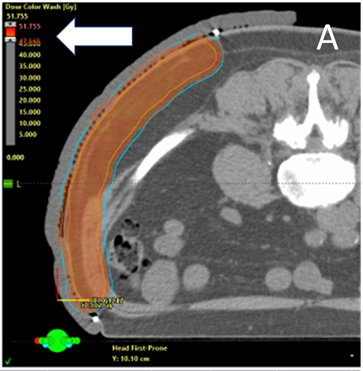

MV photons: MV photons penetrate more deeply that SXRT and electrons. The exit beam in deeper tissues beyond the target must be considered. Figure 4A details a case study where astute nursing helped predict and explain the acute reaction from MV photons.

A A 70-year old man with multiple recurrent melanoma arising within a large resection scar on the left flank required radical RT to control any future recurrence. Screen shot A shows the prone planning CT scan with an axial cut through the abdomen. The blue line is the PTV. The dose colour wash is set to 47.5Gy (white arrow) which is 95% of the prescribed dose of 50Gy. There is good coverage of the PTV. This plan was accepted by the RO.

B An astute nurse asked the planning team to provide a plan with the lower bar of the dose colour wash set to half the prescribed dose. Screen shot B shows the same axial cut as A but with the lower dose range set to 25Gy, or half the prescribed dose (white arrow). Note that some of the large colon (red arrow) is included in the volume getting this dose. The large colon is lined by gut epithelium, a hierarchically organised cell population. A possible side effect of treatment could be diarrhoea. The nurse was able to predict this and educate the patient as to why it may occur. The nurse could then pay particular attention to whether this symptom was starting and could quickly institute appropriate care if and when it happened to ensure timely course completion.

Figure 4 Predicting acute reactions from MV photons using the planning dose colour wash.